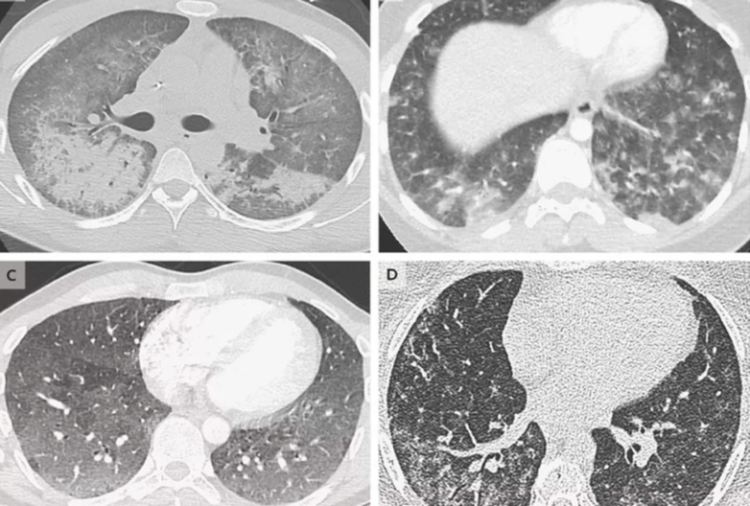

Докато разследването продължава, поредица от статии, публикувани в The New England Journal of Medicine (NEJM), днес погледнаха по-дълбоко в проблема. Една от статиите дава по-ясна представа за демографските показатели на болестта, като се съсредоточава върху 53 случая, докладвани от щатите Уисконсин и Илинойс. Цифрите очертават сурова картина.

Изследователите установили, че от от всички случаи, 83 процента са мъже, а средната възраст на пациентите е едва 19 години. Осемдесет и четири процента от пациентите съобщават, че употребяват тетрахидроканабинол (известен още като THC), един от най-често срещаните и активни канабиоиди, преди да се появят симптомите им. Почти всички страдат от дихателни и стомашно – чревни проблеми, а 94 процента са хоспитализирани. Един от тях е починал.